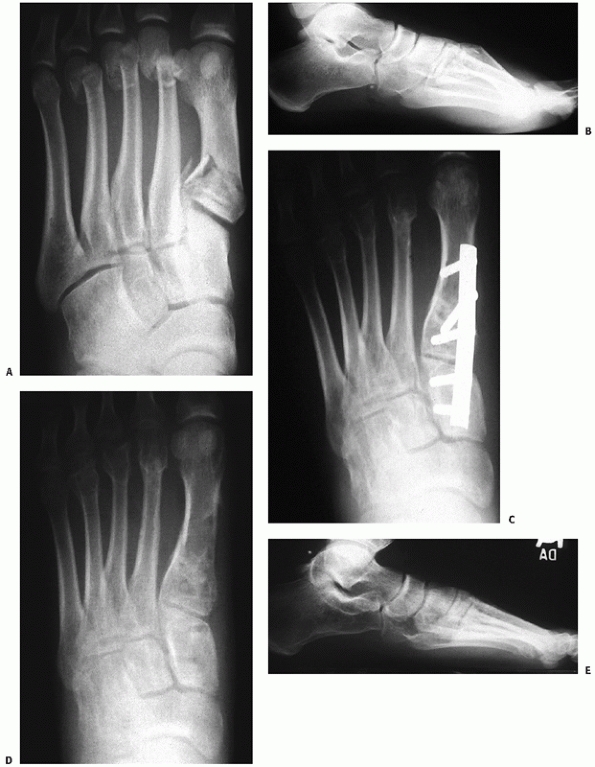

![]() |

FIGURE 60-16 Restoration of nutcracker fracture of cuboid. A. Typical fracture appearance in anteroposterior and lateral planes. B. Placement of external fixator to restore normal anatomy. Any defect should be filled with cancellous graft. C. Internal stabilization is possible with a 3.5-mm tubular plate to maintain reduction and position of cuboid.